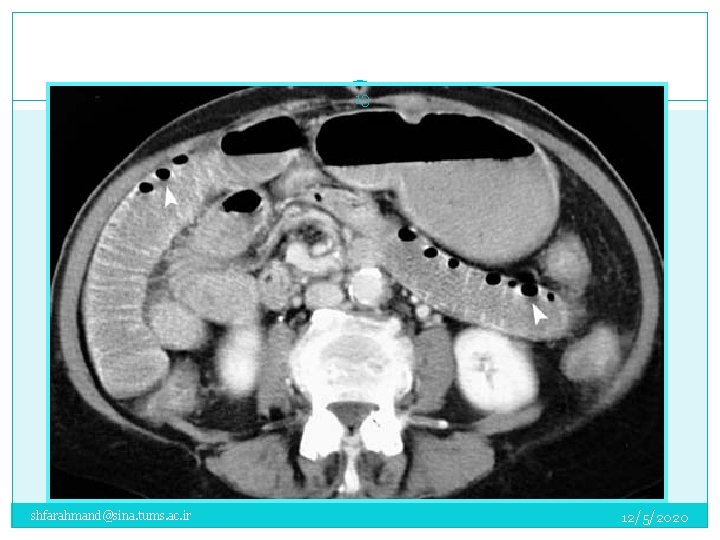

ﺍﺳکﻦ ﺷکﻢ CT 18 shfarahmand@sina. tums. ac. ir 12/5/2020